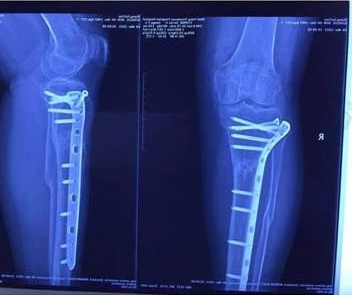

骨折延迟愈合

术后九个月未愈合 冲击波治疗后二个月

按骨折的部位和类型,经过治疗后,未能在平均时间内愈合,骨折断端仍未出现骨折连接,称为骨折延迟愈合。ESWT 具有成骨作用,在治疗骨折延迟愈合方面应用越来越广泛,治疗胫骨、跖骨、股骨等骨折延迟愈合时,总体有效率 70%~90%.

根据临床及叉线的证据,骨折治疗后超过一般愈合时间且再度延长治疗时间仍达不到骨性愈合,显示骨修复已停止,可诊断为骨折不愈合,骨折不愈合的最终表现为假关节形成。ESWT治疗骨折不愈合的原理与治疗骨折延迟愈合类似,并且具有良好效果。